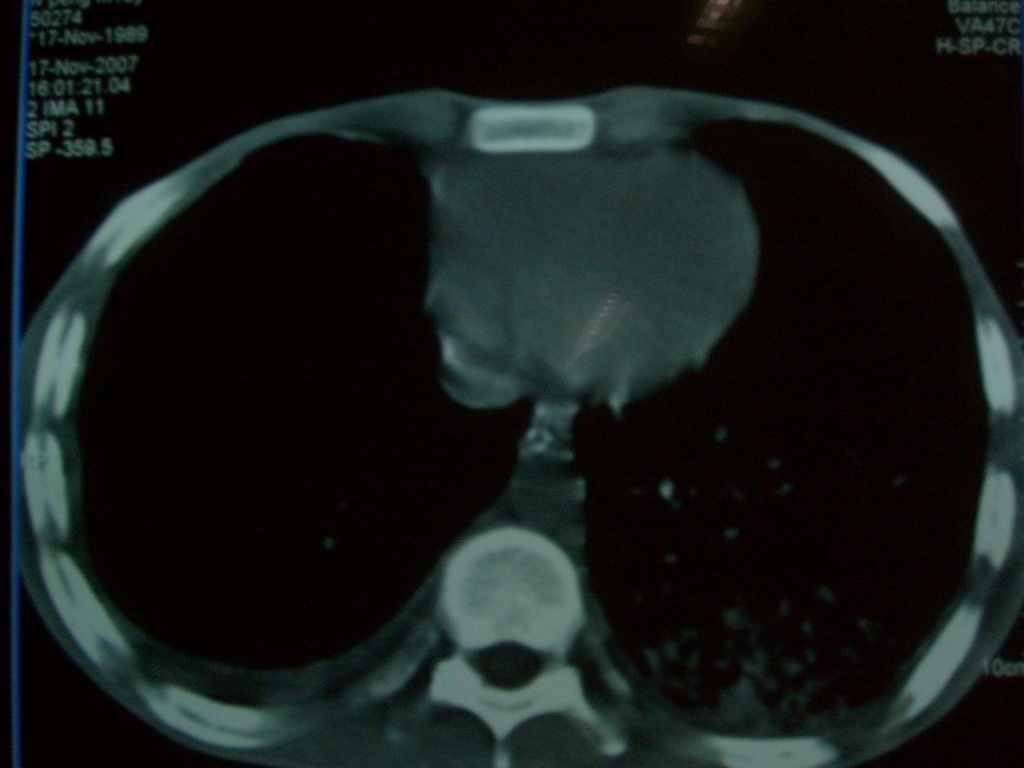

标题: CT10510:男.18岁,咳嗽咳痰两月.(有病理) [打印本页]

标题: CT10510:男.18岁,咳嗽咳痰两月.(有病理)

双肺布满大片状实变及网格状结节影,内参杂大小不等的气囊及空气支气管征,心脏增大。考虑:1 全身结缔组织疾病—系统性红斑狼仓?2 肺泡蛋白沉积症合并感染!

双肺布满大片状实变及网格状结节影,内参杂大小不等的气囊及空气支气管征,双侧胸膜腔少量积液,双下肺近膈面透亮度尚可,病人较年轻,病变较重(不知为什么上胃管?)考虑:1.胶原病肺部改变,2.组织细胞病x。结合实验室检查。

首先考虑组织细胞x病。两肺中上肺野多发囊腔,中下肺野内见多发小结节,并可见肺间质增厚。患者是男性,年龄较小。胶原性病变比较多见的类风湿、系统性红斑狼疮和硬皮病临床和影像均不是很支持,类风湿和系统性红斑狼疮的肺部表现最常见的是胸腔积液,硬皮病可见食管的扩张。

肺内多发斑片状、结节状、融合大片状及网格状影,多发薄壁空腔影,胸膜肥厚,纵隔、气管右移,考虑ⅲ型肺结核,多发空洞,继发肺间质纤维化。

双肺结核并播散.患者以肠梗阻入院,手术为肠结核.术后咳嗽做ct检查.